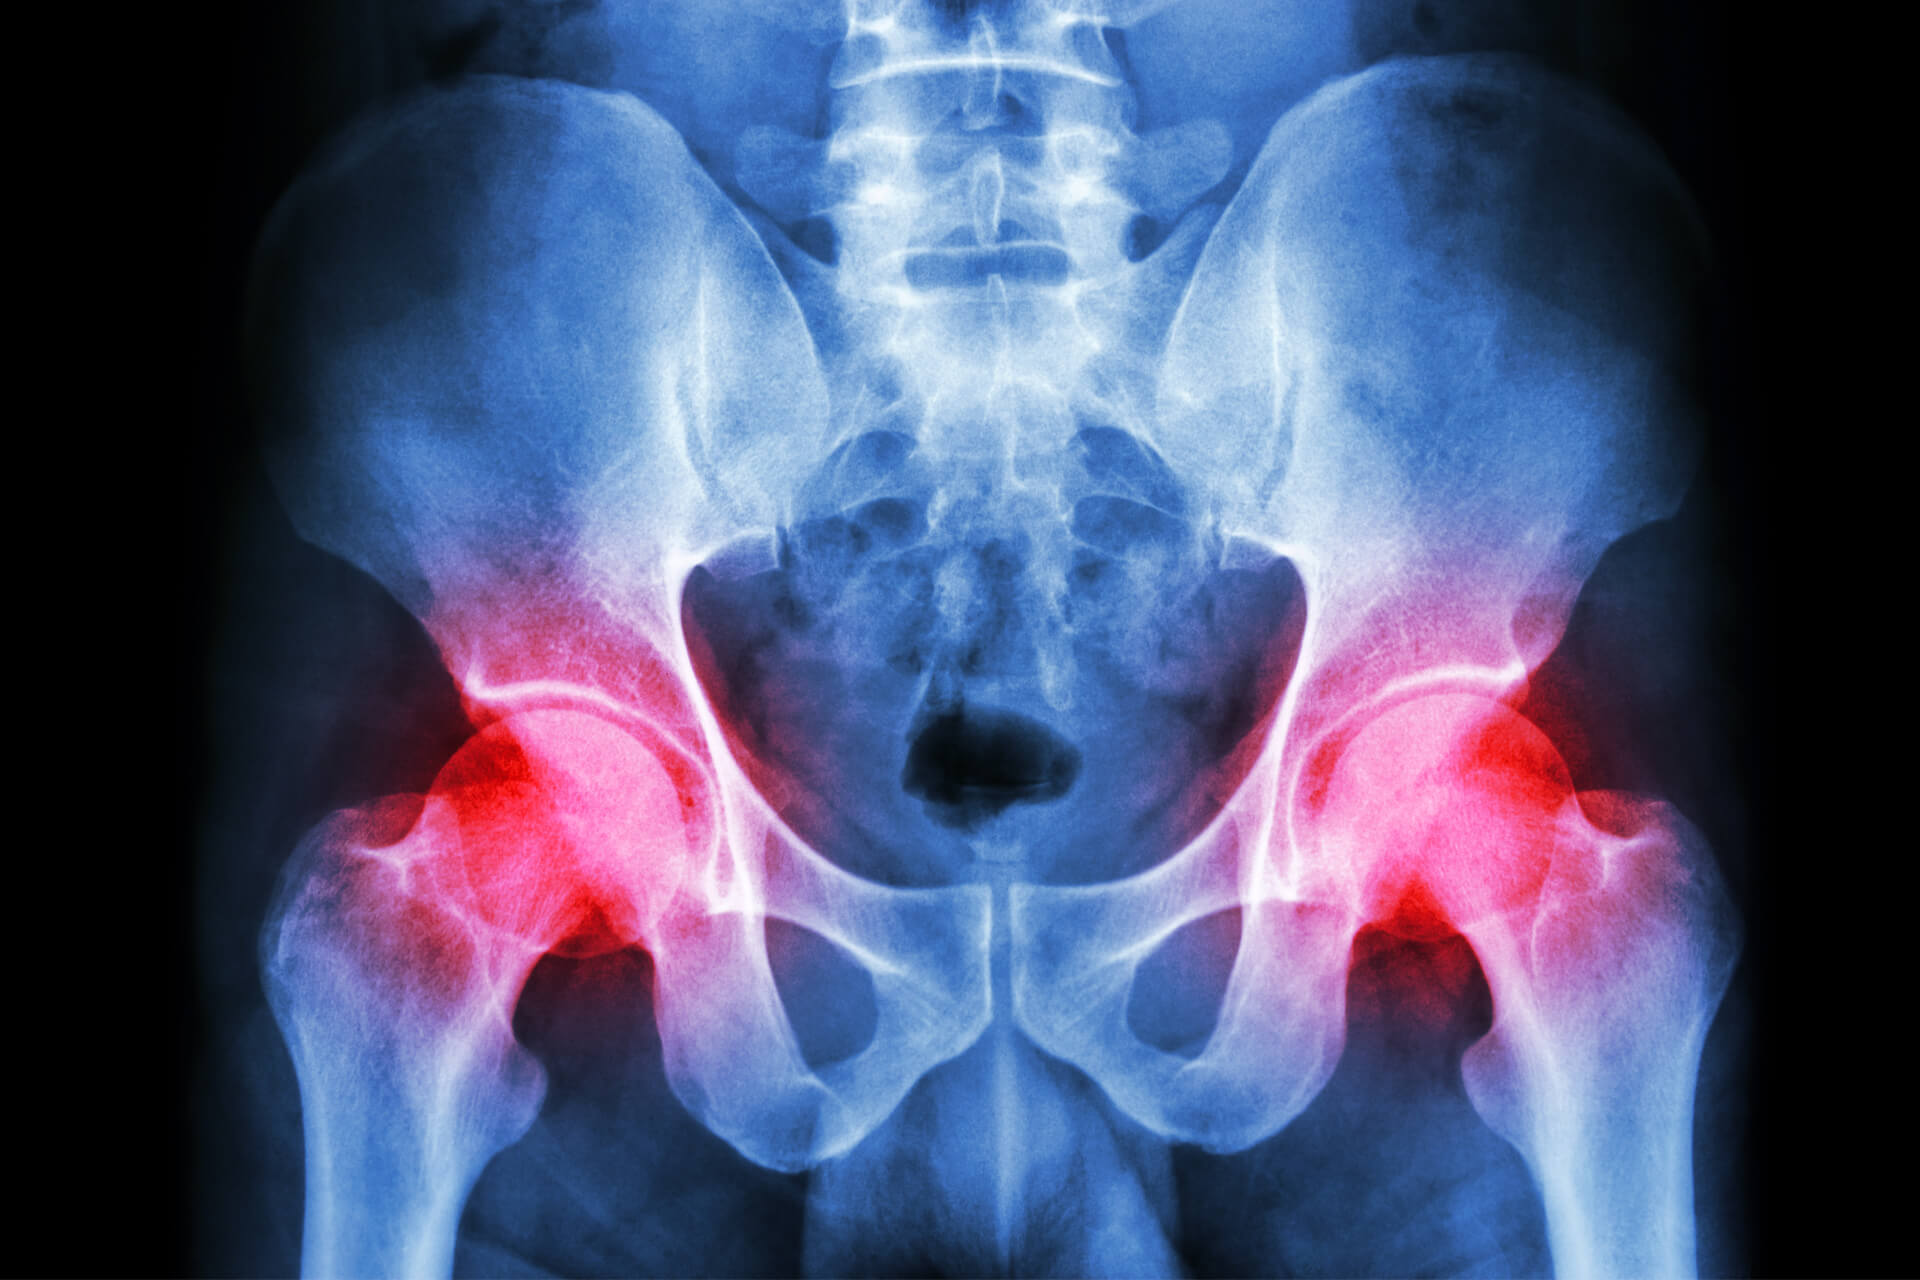

L’osteoartrosi dell’anca, più comunemente chiamata artrosi dell’anca, è una malattia degenerativa dell’articolazione composta tra il femore e il bacino; l’erosione della cartilagine che riveste tale articolazione causa un fenomeno infiammatorio che diventa una delle cause di dolore riferite dai pazienti.

Cosa comporta l’artrosi dell’anca? Il dolore inguinale che si irradia fino al ginocchio e che spinge il paziente a recarsi dallo specialista, causa una limitazione funzionale dell’arto inferiore con progressiva riduzione delle attività della vita quotidiana e impatto sulla qualità di vita.